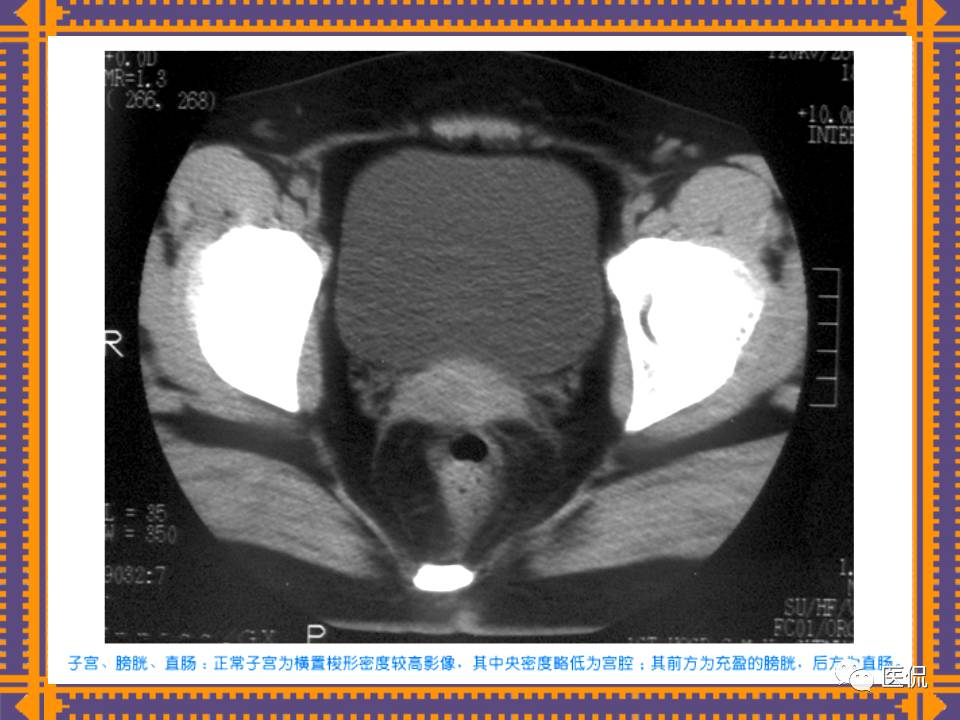

这篇PPT对男性生殖系统疾病:前列腺增生、前列腺癌;女性生殖系统疾病:子宫肌瘤、子宫癌、卵巢囊肿和卵巢肿瘤以及腹膜后间隙疾病进行了详细讲解。